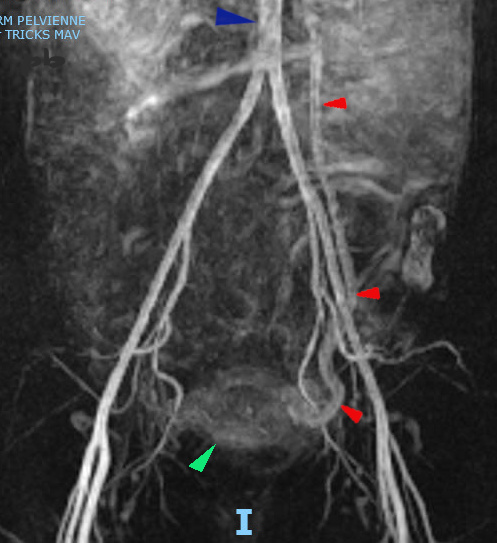

15 – Faux diagnostic de MAV

(même patiente que 14)

IRM coupe frontale – séquence vasculaire injectée (Tricks) temps artériel tardif.

Opacification précoce de la veine ovarienne gauche (►).

Utérus encore peu opacifié (►).

Echographie normale un mois plus tard, sans traitement.

Il s’agissait donc des modifications vasculaires habituellement rencontrées en cas de rétention trophoblastique (hypervascularisation de type utéro-placentaire), et non d’une malformation artério-veineuse (MAV).

Aorte (►)